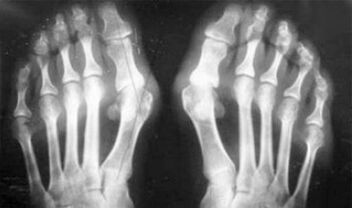

Der Unterschied zwischen Arthritis und Arthrose der Finger und Hände der Hände besteht darin, dass die erste Krankheit geheilt und die zweite nicht. Bei Arthritis wird die Synovialschale und die Kapsel des Gelenks berührt.

Die Niederlage des Knorpels und des Knochengewebes erfolgt nur in den späten Stadien in einem vernachlässigten Zustand. Bei Arthrose ist das Knorpelgewebe zuerst betroffen, und dann ist die Entzündung der Synovialmembran einen sekundären Ursprung, dh sich vor ihrem Hintergrund.